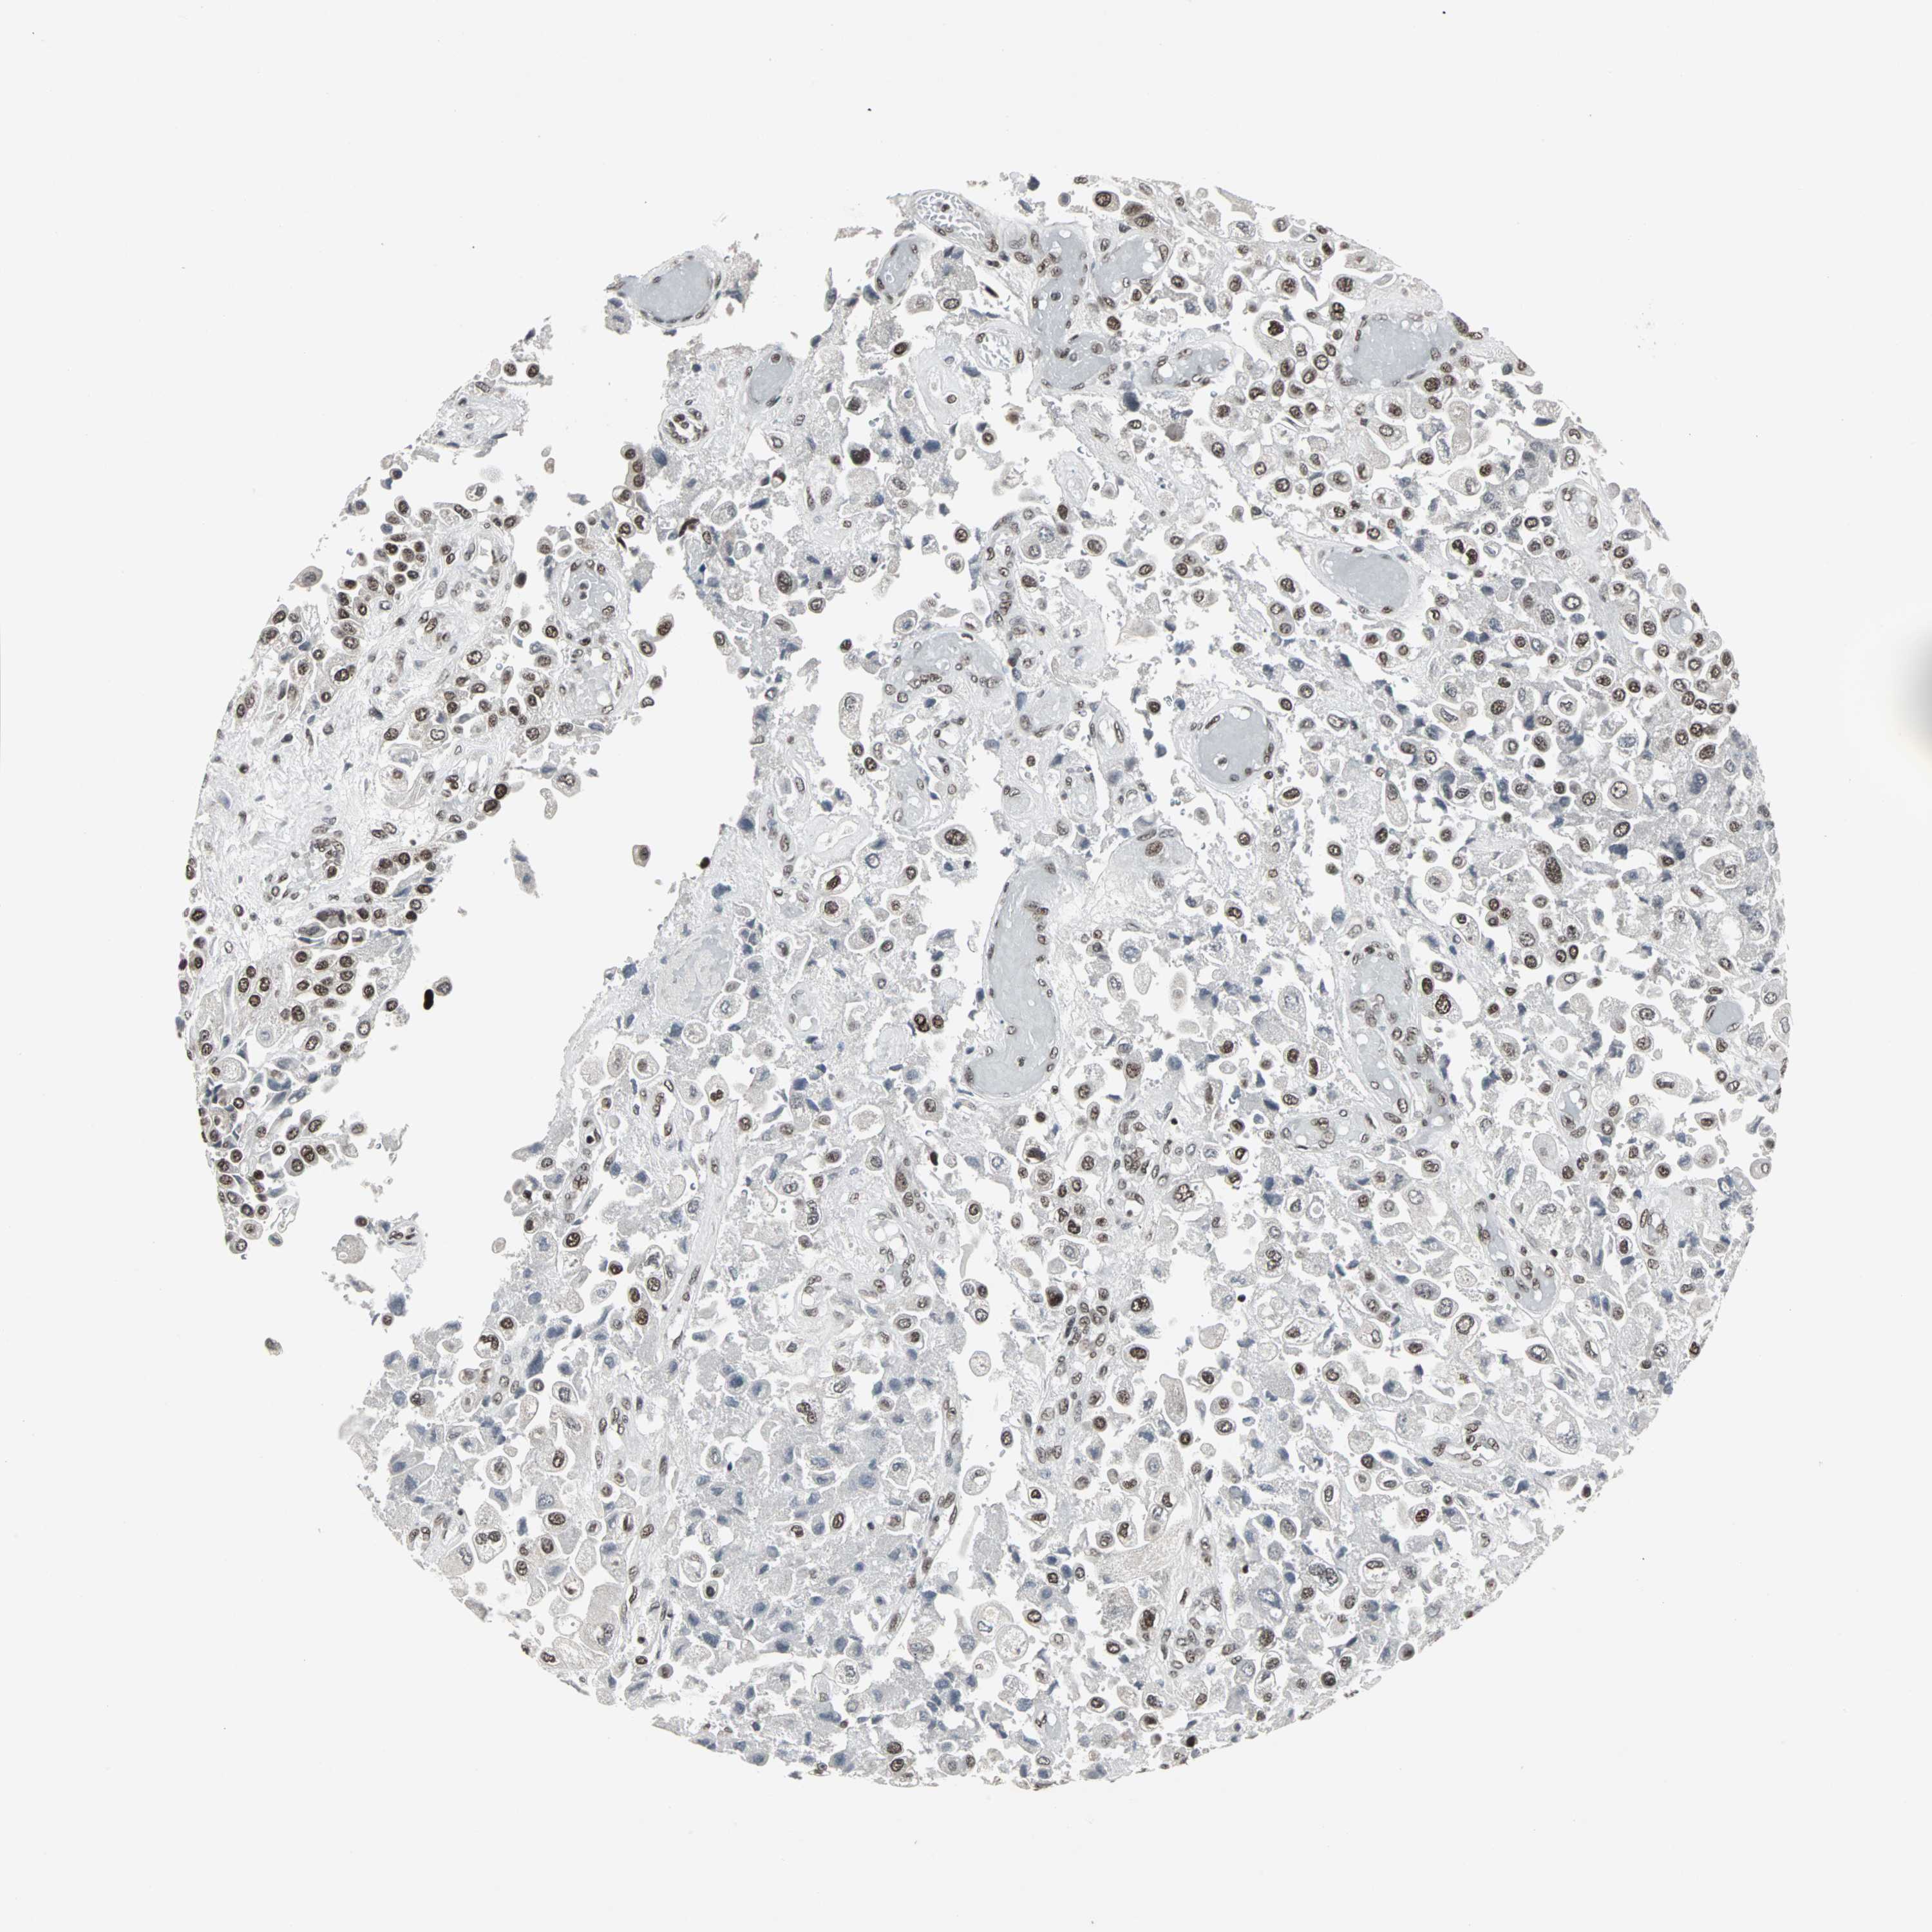

UROTHELIAL CANCER - Protein expressioni

A mouse-over function shows sample information and annotation data. Click on an image to view it in a full screen mode. Samples can be filtered based on level of antibody staining by selecting one or several of the following categories: high, medium, low and not detected. The assay and annotation is described here.

Note that samples used for immunohistochemistry by the Human Protein Atlas do not correspond to samples in the TCGA dataset.

Antibody stainingi

Antibody staining in the annotated cell types in the current human tissue is reported as not detected, low, medium, or high, based on conventional immunohistochemistry profiling in selected tissues. This score is based on the combination of the staining intensity and fraction of stained cells.

Each image is clickable and will lead to virtual microscopy that enables deeper exploration of all samples and also displays staining intensity scores, fraction scores and subcellular localization as well as patient and tissue information for each sample.

Antibody HPA006782

Staining

High

Medium

Low

Not detected

Intensity

Strong

Moderate

Weak

Negative

Quantity

>75%

75%-25%

<25%

None

Location

Nuclear

Cytoplasmic/membranous

Cytoplasmic/membranous,nuclear

Urothelial carcinoma, High grade

Urothelial carcinoma, Low grade